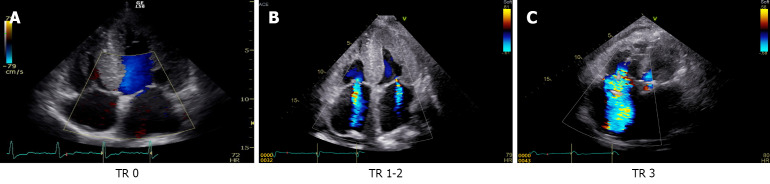

Methods: We retrospectively analyzed 179 chronic HF patients who underwent echocardiography and CT within one year. Right HF severity was classified into three grades. Liver CT images at the paraumbilical vein level were used to develop a ResNet-based machine learning model to predict tricuspid regurgitation (TR) severity. Model accuracy was compared with that of six gastroenterology and four radiology experts.